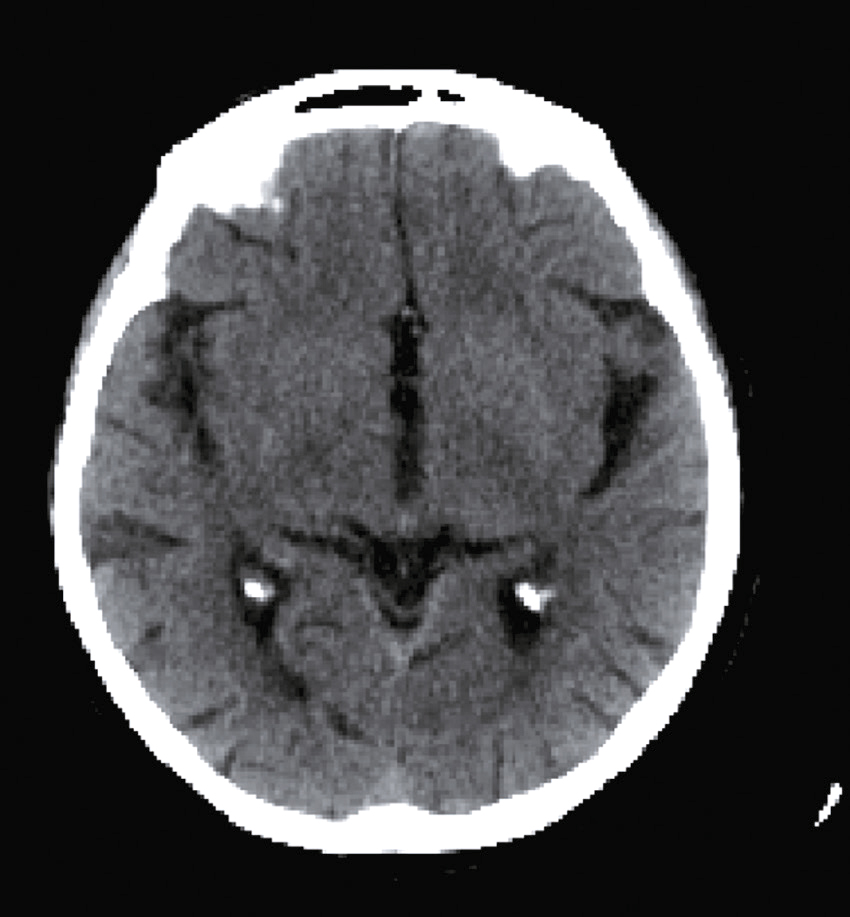

Vous débutez un traitement par benzodiazépine, vitaminothérapie B1, B6, PP, réhydratation par sérum salé et immunoglobulines polyvalentes intraveineuses associées à une héparine de bas poids moléculaire à dose isocoagulante. Le lendemain matin, le patient s’est aggravé d’un point de vue clinique. Il n’a plus d’hallucination visuelle mais il présente maintenant une tétraparésie évaluée à 3/5 avec ataxie des quatre membres, une dysarthrie, des troubles de la déglutition, et une ophtalmoplégie bilatérale. Un bilan biologique a été prélevé avant votre arrivée : numération formule sanguine : Hb : 13,8 g/dL, leucocytes : 8 600/ mm3, plaquettes : 332 000/mm3, ionogramme sanguin : Na+ : 142 mmol/L, K+ : 4,2 mmol/L, clairance de la créatininémie : 92 mL/min, glycémie : 5,8 mmol/L, transaminases, phosphatases alcalines, bilirubines et γ-GT normales, CRP : 3 mg/L.

Une IRM cérébrale a été également réalisée (fig. 31.4). Quelle est la séquence présentée ?

L'image montre une IRM (Imagerie par Résonance Magnétique) du cerveau humain en coupe axiale, c'est-à-dire une vue transversale du cerveau prise horizontalement. Cette image est particulièrement intéressante car elle permet de visualiser les structures internes du cerveau avec une grande précision. On peut observer les globes oculaires en haut de l'image, qui apparaissent comme deux cercles blancs. Les différentes zones du cerveau sont visibles, avec des variations de teintes qui indiquent les différentes densités des tissus cérébraux. La région centrale lumineuse correspond au tronc cérébral, une structure cruciale pour de nombreuses fonctions vitales. Les zones plus sombres autour du tronc cérébral représentent les hémisphères cérébraux. Cette image est utilisée pour diagnostiquer et évaluer diverses conditions neurologiques, telles que les tumeurs, les accidents vasculaires cérébraux, les infections, et les anomalies structurelles. L'IRM est une technique non invasive qui utilise des champs magnétiques et des ondes radio pour produire des images détaillées des organes et des tissus internes.

- A T1

- B écho de gradient

- C T2

- D T2/FLAIR

- E diffusion